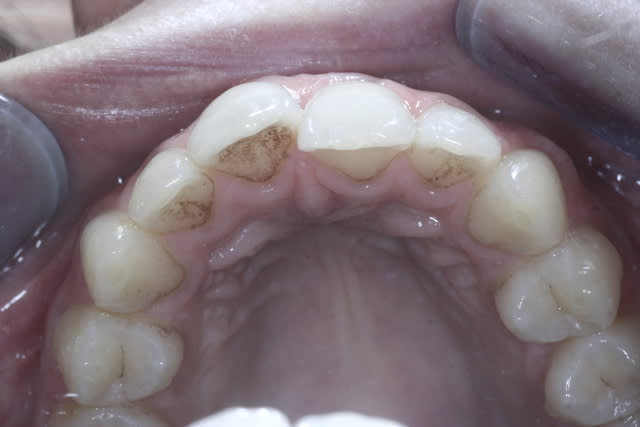

Cett jeune patiente refuse l'ODF "classique" mais veut faire qqchose pour corriger le chevauchement.

QQun pourrait me dire comment faire, je pensais un traitement comme le propose Danche mais pourriez-vous me préciser les références du matériel utilisé et la façon de faire ?